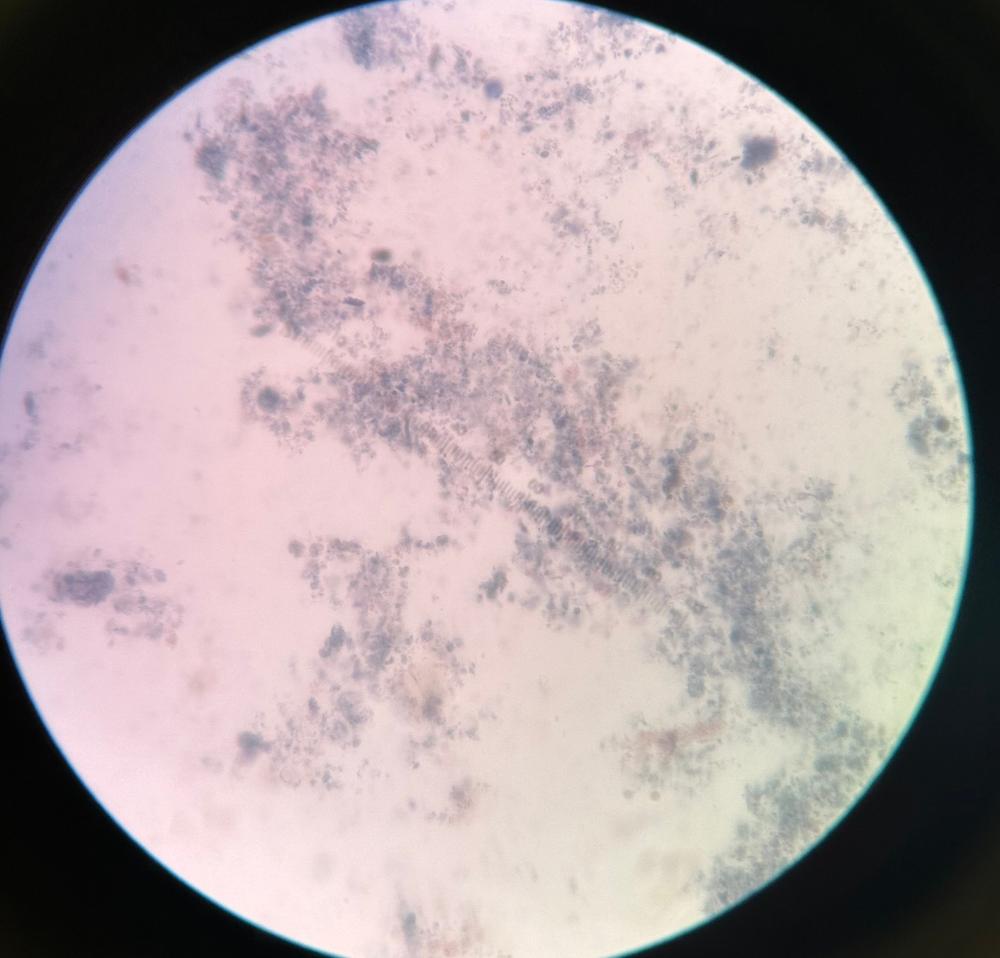

Plasmodium Vivax Blood Smear